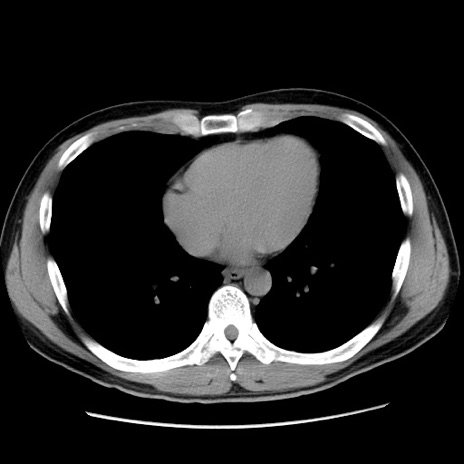

症例36(横断像)

【症例】20歳代 男性

【主訴】心窩部痛

【現病歴】今朝より上腹部痛あり。一旦軽快していたが再度出現したため救急要請。昨日夕に白身の魚を含む刺身を食べた。

【身体所見】BP 136/89mmHg、HR 74/min、BT 37.0℃、腹部:膨満、軟、心窩部に圧痛あり。反跳痛なし、筋性防御なし、腸雑音やや亢進あり。

【データ】WBC 17700、CRP 0.48